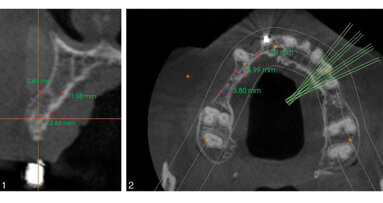

TORONTO, Ontario, CANADA: ClaroNav announced today (June 3, 2020) that it has obtained Health Canada and CE Mark approvals to expand the indications for use...

TORONTO, Ontario, CANADA: Azento single tooth replacement solution is transforming the digital implant workflow by streamlining implant planning, purchasing...